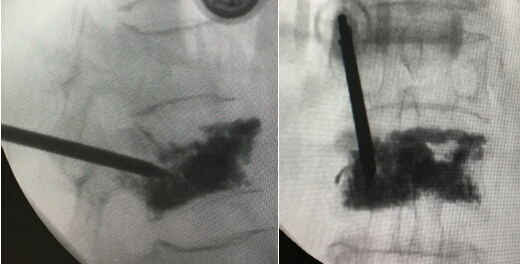

• 我院脊柱外科一区成功开展广西首例弯角椎体成形术

我院脊柱外科一区成功开展广西首例弯角椎体成形术

8月9日下午,我院脊柱微创团队在陈远明主任的带领下,借助先进的弯角椎体成形专用装置,只用不到一小时的时间,成功为患有骨质疏松性L1椎体新...

发布时间:2016-08-10 来源: